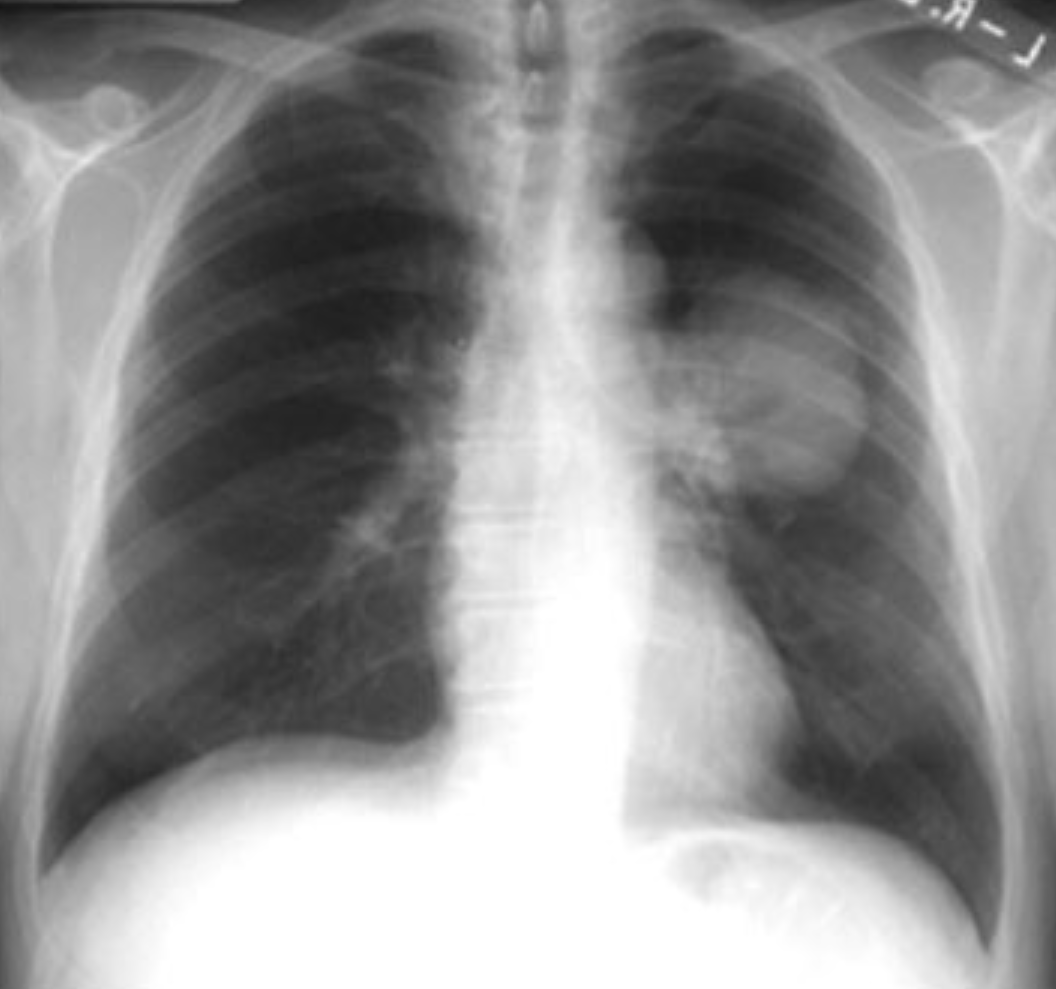

Starfsemi samrunaaðila felst í að veita læknisfræðilega myndgreiningarþjónustu, en undir hana falla m.a. tölvusneiðmyndarannsóknir, röntgenrannsóknir, ómun, segulómun og skyggnirannsóknir, er skýrt á vef Samkeppniseftirlitisins.

Mynd/Læknablaðið/myndskreyting/01. tbl. 95. árg 2009